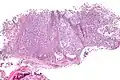

| Micrograph of a myoepithelioma. H&E stain. | |

The myoepithelial cells may be spindled, plasmacytoid, eithelioid or clear. Tubules or epithelium are absent, or present in a small amount (<5%) by definition. Tumours with myoepithelial cells and a large amount of tubules are classified as pleomorphic adenomas (which must also contain the characteristic chondromyxoid stroma, which is normally absent in myoepithelioma).

Myoepitheliomas are diagnosed from an examination of the tissue by a pathologist.